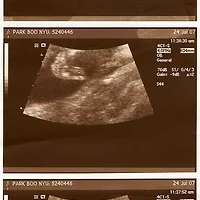

임신19주

초음파를 보면 태아가 차고, 구부리고, 구르고 때때로 손가락을 빠는 것을 볼 수 있습니다.

임신19주가 되면 아기의 표정까지 관찰할 수 있습니다.

태아의 길이는 15-16cm 정도입니다.

초음파검사를 해보면 아가가 양수를 들이 마시고 내 보내며 가슴이 위아래로 움직이는 게 보입니다.

또한 발로 차고, 구부리고, 손가락을 빠는 등 그 외에도 다양한 태아의 운동을 관찰할 수 있답니다.